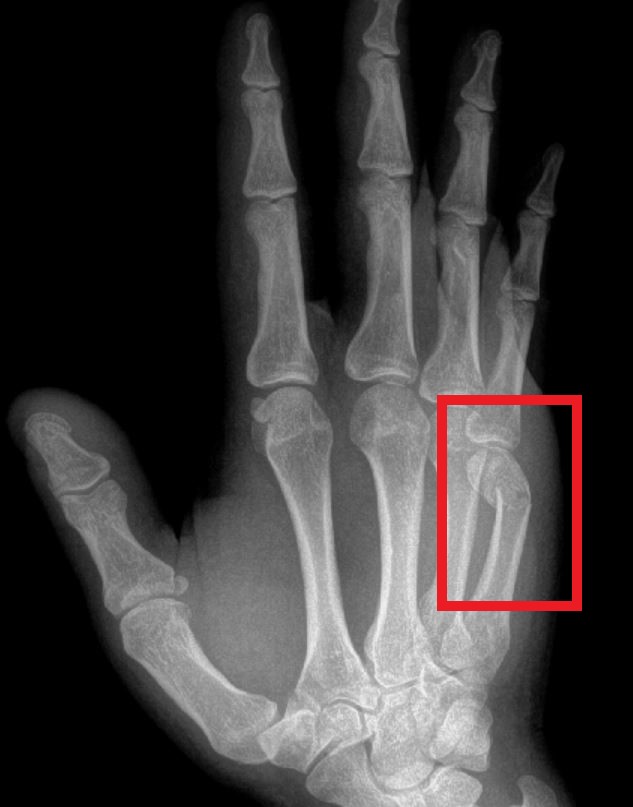

A boxer’s fracture specifically is a fracture of the fifth metacarpal neck. The hand has five metacarpals, one for each finger and the thumb. The metacarpals make up the bony architecture of the hand between the wrist and the fingers. The fifth metacarpal is at the base of the small finger, or pinkie. The metacarpal neck is the part of the bone between the head and shaft of the metacarpal, closest to the MCP “knuckle” joint.

A word of caution: not all fifth metacarpal fractures are boxer’s fractures. Inexperienced clinicians often mislabel a fifth metacarpal shaft fracture as a “boxer’s fracture.” Fractures involving the shaft of the metacarpal can result in significant hand impairment if not treated adequately. Consider consultation with an orthopedic hand specialist to guide your hand care appropriately.